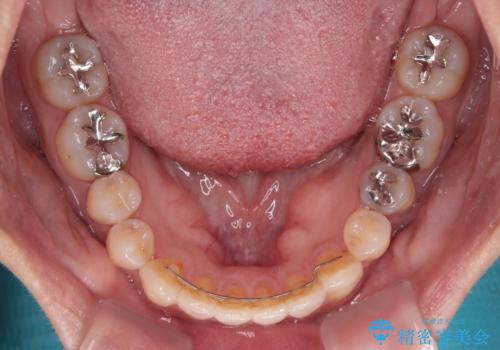

開咬と変色した前歯 インビザライン矯正とオールセラミッククラウン治療

- 前歯の開咬と失活により変色した前歯を気にして来院された患者様です。

開咬の治療は、前歯を閉じるように引っ張り出すよりも、上下臼歯を圧下(骨内にめり込ませる)させることで進める方が長期的に安定した歯列を維持できます。

インビザラインは臼歯の圧下を効果的に行えるため、インビザラインを用いて矯正治療を行うこととしました。

矯正治療が概ね終了した時点で前歯をオールセラミッククラウンにて補綴治療を行い、その後インビザラインにて細かい部分を仕上げていくことしました。